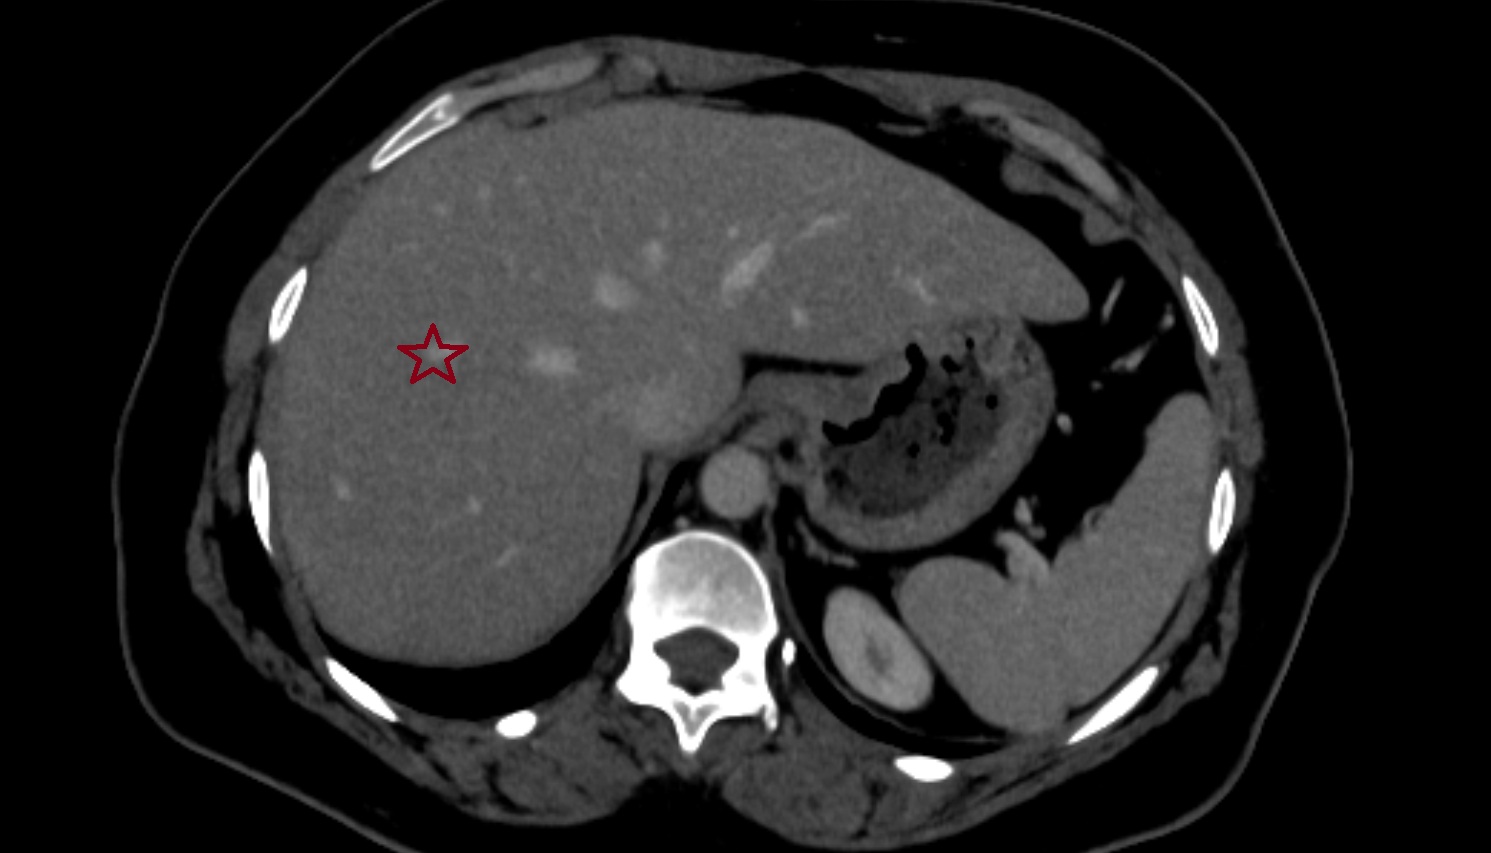

CT image

Liver Segment VIII – Right anterosuperior segment  CT  axial  anatomy  image